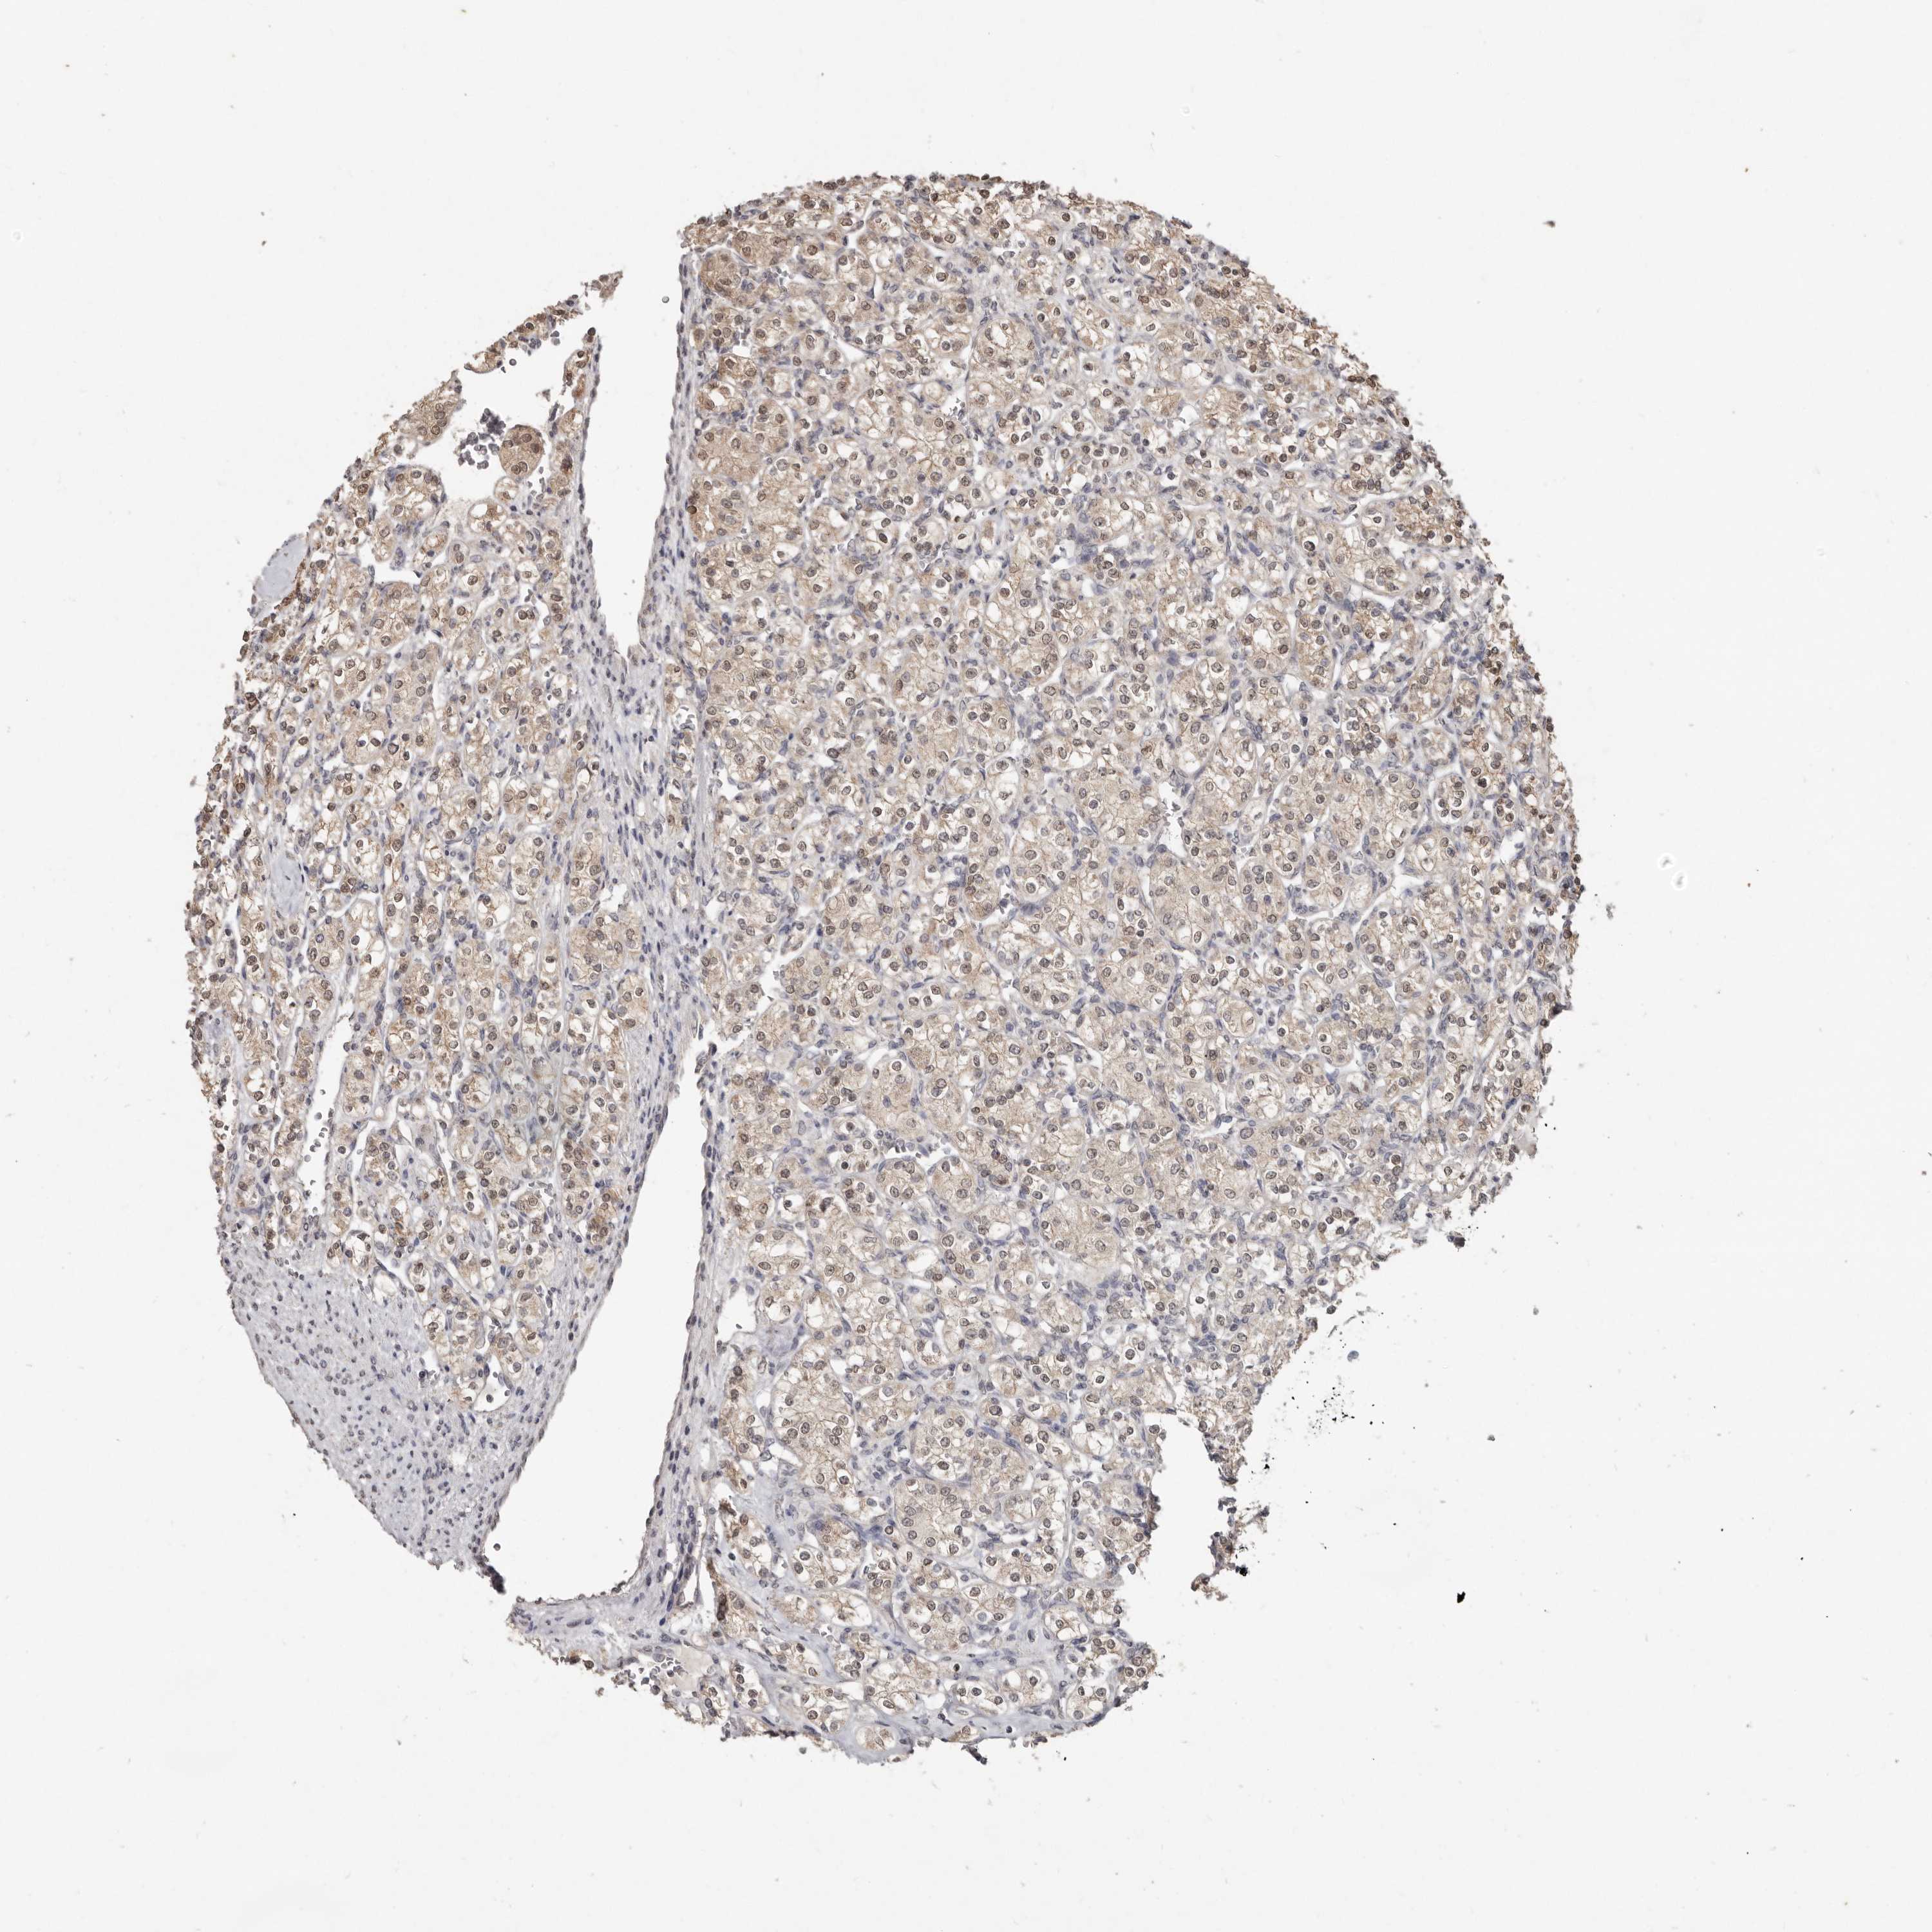

KIDNEY RENAL CLEAR CELL CARCINOMA (VALIDATION) - Interactive survival scatter ploti

The Survival Scatter plot shows the clinical status (i.e. dead or alive) for all individuals in the patient cohort, based on the same data that underlies the corresponding Kaplan-Meier plots. Patients that are alive at last time for follow-up are shown in blue and patients who have died during the study are shown in red.

The x-axis shows the expression levels (FPKM) of the investigated gene in the tumor tissue at the time of diagnosis. The y-axis shows the follow-up time after diagnosis (years). Both axes are complimented with kernel density curves demonstrating the data density over the axes. The top density plot shows the expression levels (FPKM) distribution among dead (red) and alive patients (blue). The right density plot shows the data density of the survived years of dead patients with high and low expression levels respectively, stratified using the cutoff indicated by the vertical dashed line through the Survival Scatter plot. This cutoff is automatically defined based on the FPKM cutoff that minimizes the p-score. The cutoff can be changed by dragging the vertical line or by entering a cutoff value in the square labeled "Current cut-off".

Under the Survival Scatter plot the p-score landscape (black curve; left axis) is shown together with dead median separation (red curve; right axis). Dead median separation is the difference in median mRNA expression between patients who have died with high and low expression, respectively. It is calculated as follows: median FPKM expression of dead patients with high expression - median FPKM expression of dead patients with low expression. This is intended to aid the user in visually exploring custom cutoffs and the associated p-scores and dead median separation.

Individual patient data is displayed and can be filtered by clicking on one or more of the category buttons on the top of the page. Categories describing expression level and patient information include: high, low, alive, dead, female, male and tumor stages. The scale of the x-axis can be toggled between linear and log-scale by clicking on the "x log" button. Mouse-over function shows TCGA ID, patient information and mRNA expression (FPKM) for each patient.

& Survival analysisi

Kaplan-Meier plots summarize results from analysis of correlation between mRNA expression level and patient survival. Patients were divided based on level of expression into one of the two groups "low" (under cut off) or "high" (over cut off). X-axis shows time for survival (years) and y-axis shows the probability of survival, where 1.0 corresponds to 100 percent.

LINGO2 is not prognostic in Kidney Renal Clear Cell Carcinoma (validation)

TCGA RNA samplesi

RNA-seq data is reported as average FPKM (number Fragments Per Kilobase of exon per Million reads), generated by the The Cancer Genome Atlas (TCGA) .

Normal distribution across the dataset is visualized with box plots, shown as median and 25th and 75th percentiles. Points are displayed as outliers if they are above or below 1.5 times the interquartile range. FPKM values of the individual samples are presented next to the box plot.

Average pTPM 0.0

Number of samples 100